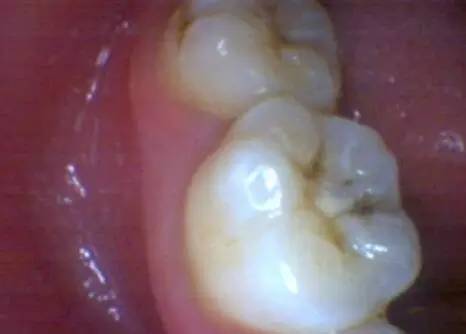

让我们来看看尽腐质后的情况。

窝洞不小吧?这个还是换了不同型号的球钻,最后深部用的是微创球钻尽量多的保存好的牙体后的洞形。

两颗牙齿补完之后的样子,这样他就可以安心在美国读书了。